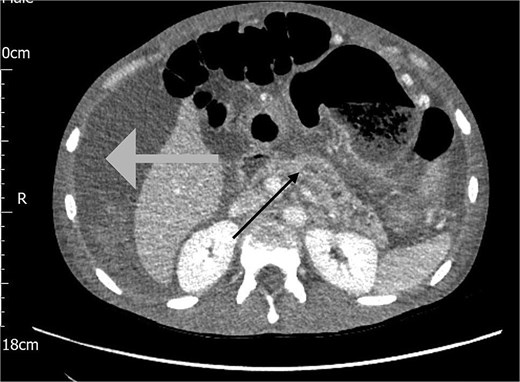

The following day, the ascites recurred, accompanied by a significant drop in haemoglobin from 127 to 81 g/L. A repeat CT Abdomen Pelvis was performed which revealed a large volume of haemorrhagic ascites with no active extravasation, and an irregular dilated pancreatic duct, as shown in Fig. 2.

CT scan of the abdomen showing haemorrhagic ascites in the perihepatic area (grey arrow) and an irregular dilated pancreatic duct (black arrow).